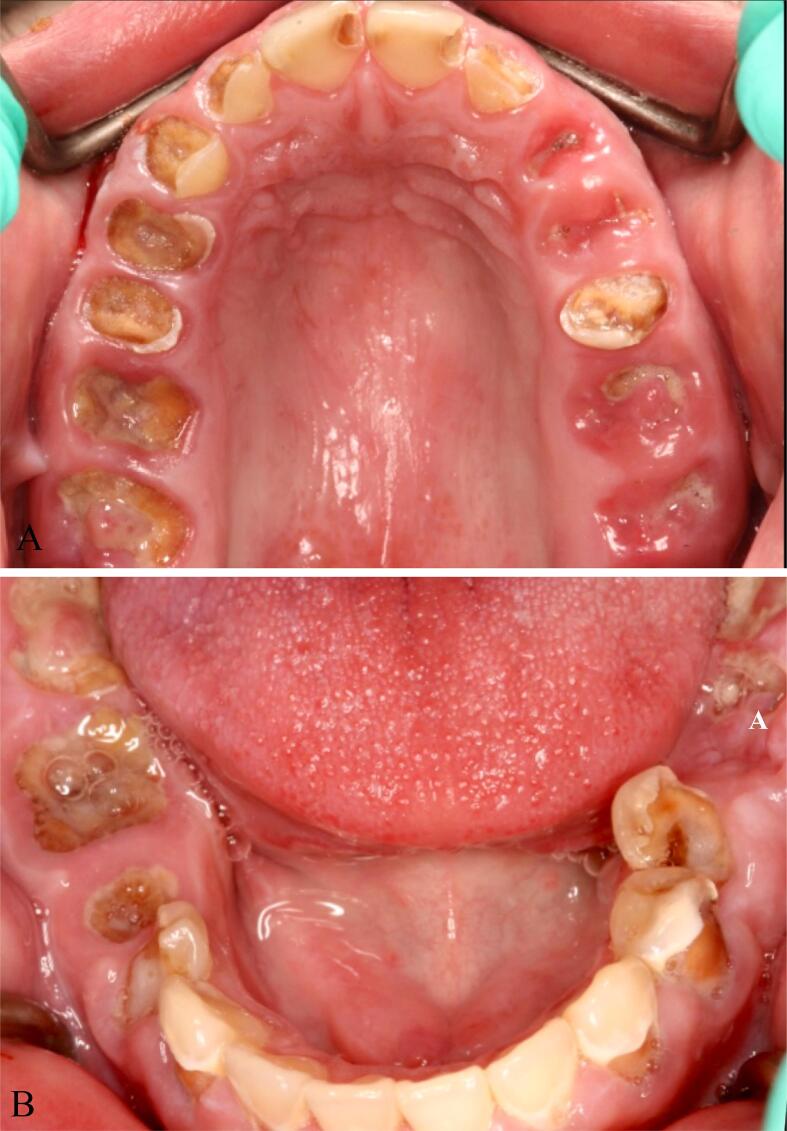

Fig. 2.

Pre-treatment intraoral occlusal view of maxillary and mandibular arches presenting “meth mouth”. Remaining roots, leathery and rampant brown carious lesions, erosion, plaque accumulation, calculus, missing tooth and periodontal inflammation are shown. A, Maxilla B, mandible.